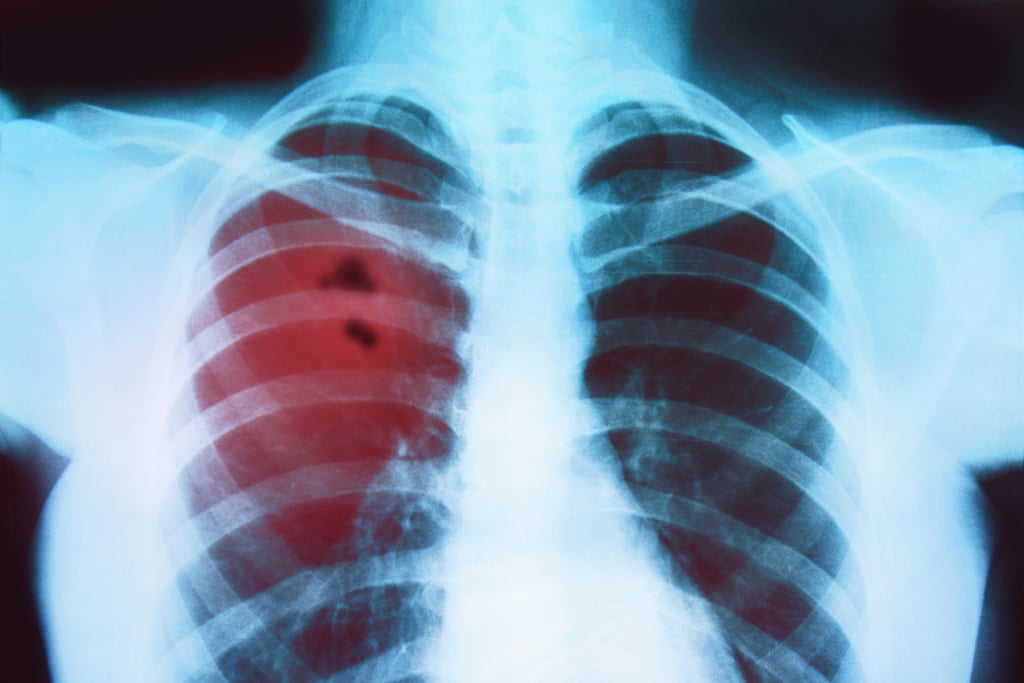

Gli esami di primo livello includono radiografia del torace e TC torace-addome con mezzo di contrasto, utili per individuare la sede e l’estensione della massa tumorale. Per confermare la diagnosi è necessario prelevare un campione di tessuto tramite biopsia, che può essere effettuata con diverse tecniche (broncoscopia, agoaspirato TC-guidato o mediastinoscopia).